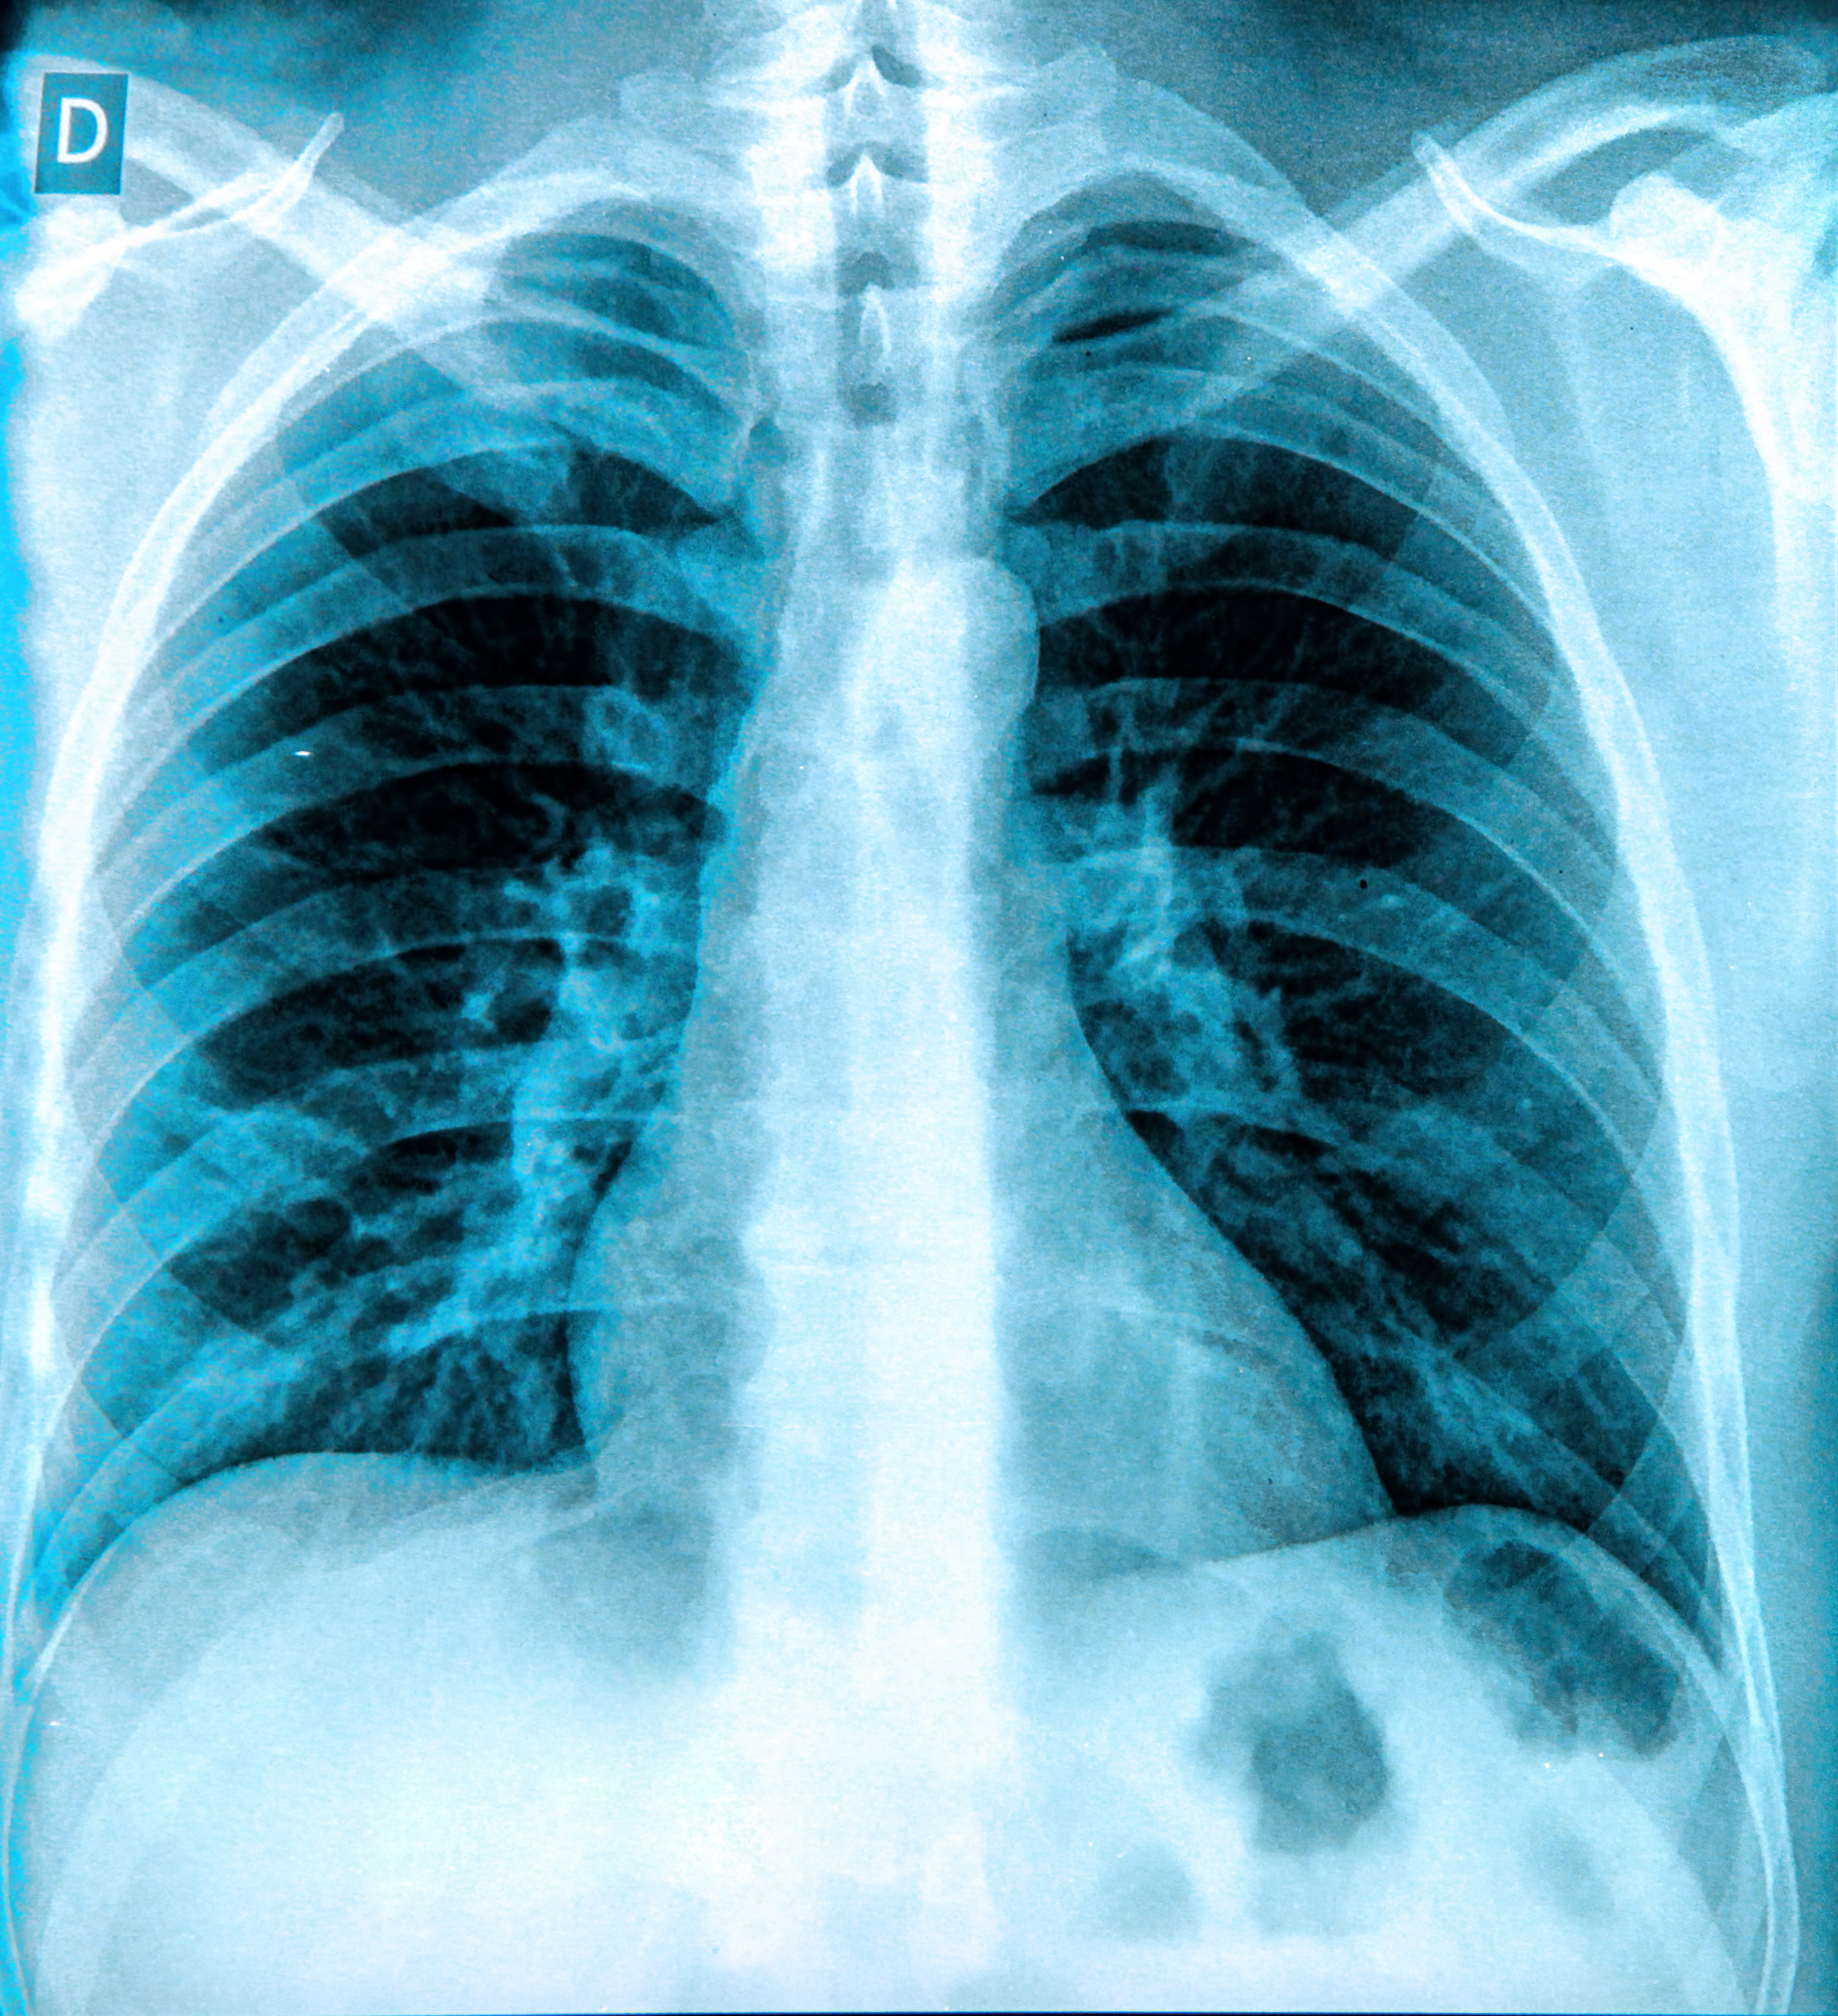

The software, qXR-LN, will serve as a “second read” alongside radiologists to improve detection of subtle lung nodules and generate evidence for future AI research, Qure.ai said. The partnership will bring AI-powered early detection to routine chest x-rays, flagging potentially cancerous lung nodules earlier and helping identify high-risk patients, the company said.